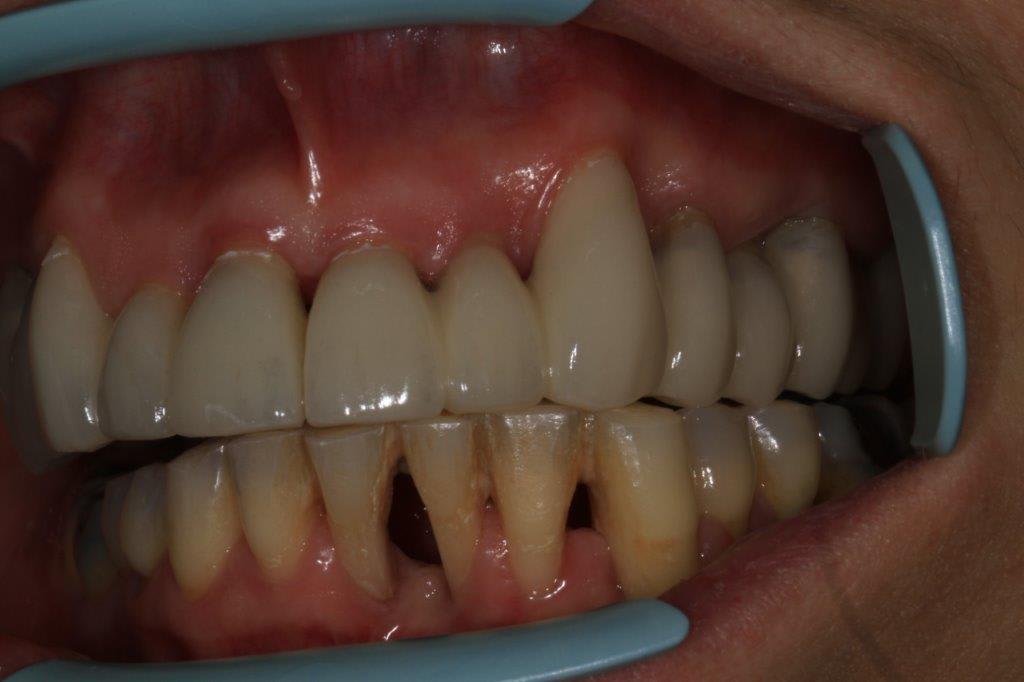

Contrôle à une semaine...

La gencive de 11 et 12 n est pas jolie .

Et ce n est pas un pb induit par la prothèse, pcq c était déjà présent sur les photos initiales .

Tu vois c est pour ça que je ne crois pas à la chimie .

T as beau la chimistrer tant que tu veux la gencive , si tu ne la fraises pas , pipée elle est , pipée elle restera.

Pas la prothèse, mais j'ai été un peu agressif à la fraise de polissage sur l'attache et effectivement ça n'est encore pas revenu, d'autant plus qu'avant les photos j'ai un peu gratouillè ala curette, les restes éventuel de ciment

Wait and see

Non non c est pas ca

C était pareil au début

A mon avis c est pcq qu il n y a pas assez d os en proximal pour soutenir la gencive

c'est clair qu'il n'y a plus beaucoup d'os, mais j'ose croire que ça va aller...